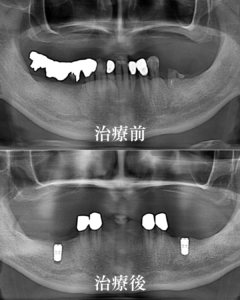

治療前後比較のレントゲン

治療前は、奥歯のブリッジの支えの歯が虫歯で溶けて完全に無くなってしまっていました。また根っこだけのような歯のカケラも見てとれると思います。

治療後は、長持ちする神経が生きている歯をメインに残して、かつ総入れ歯を最も効果的に固定ができるような配置の歯を優先的に残しています。また奥歯のインプラントも、噛む力を支える為に、直立して綺麗に配置されている状態です。